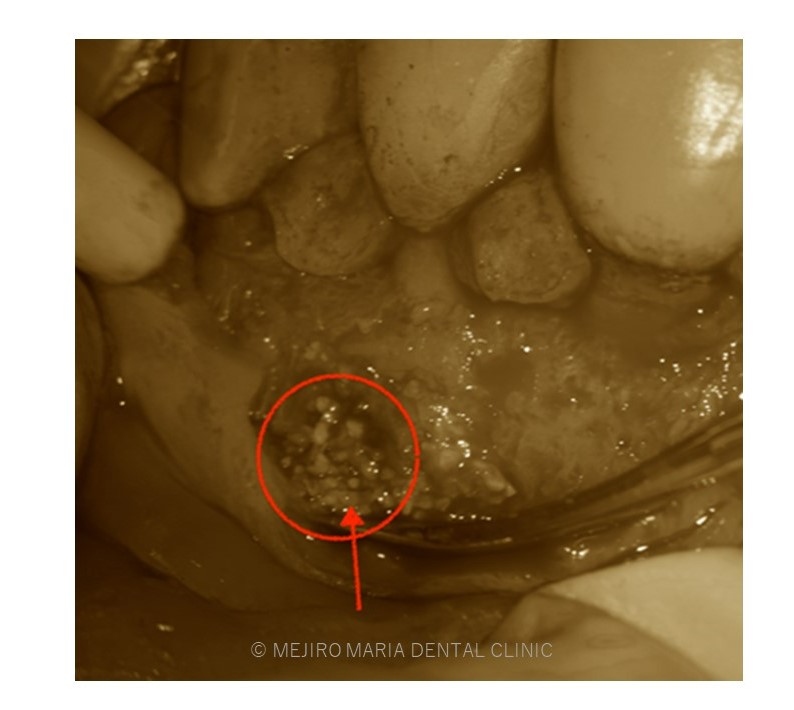

でのリカバリー_感染した人工骨の画像.jpg)

今回の症例は、他院にて歯根端切除術を行った根尖部(歯の根の先)に充填された人工骨の感染が原因と考えられます。

万が一、歯根端切除術が失敗した場合、人工骨の感染はより事態を悪化させることになります。

歯根端切除術後は術後の透過像で治癒を確認することが重要であり、感染が除去できていれば骨は患者自身の力で自然に再生を行うことになるので、人工骨を充填することはリスクが高い行為であると考えます。